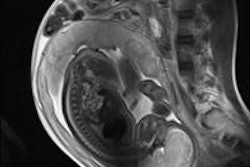

Unfortunately, those in the women's imaging field don't often see such headlines pertaining to their field. Well, prepare to say "Ooooooh." A new study from Germany discusses the use of 7-tesla MRI for the female pelvis. What did they find? And which is better, T1-weighted imaging or T2? Discover what they revealed.